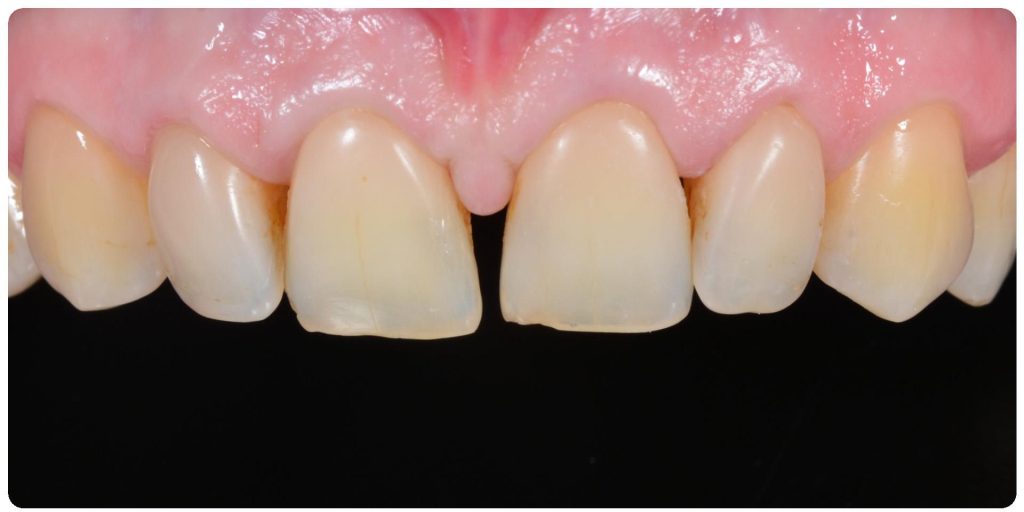

Dzięki precyzyjnej diagnostyce, doktor Magdalena Zawirska opracowała kompleksowy plan leczenia, który obejmował: stomatologię zachowawczą, periodontologię i protetykę stomatologiczną. Zastosowano licówki i korony pełnoceramiczne, przeprowadzając kompleksową rekonstrukcję zwarcia.